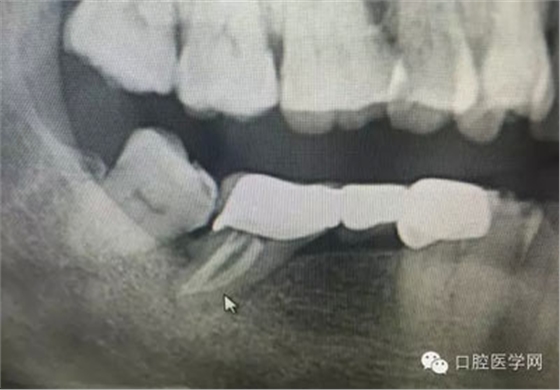

根管再治療是我們比較頭疼的,尤其是那些冠修復(fù)過的,我們有很多的麻煩需要去溝通,比如可能導(dǎo)致的側(cè)穿、可能沒有看到的腐質(zhì)、可能導(dǎo)致的崩瓷,或者是后期可能出現(xiàn)冠折......這些需要我們和患者好好的溝通。全瓷冠還好些,金屬冠根測的時候很是麻煩,總之我們做修復(fù)的時候不要單純的追求速度,追求效益,適當?shù)淖⒁庀挛覀兊幕A(chǔ)治療和設(shè)計。

這是一例外院樹脂修復(fù)后十個月出現(xiàn)牙髓炎癥狀的患者。遇到這樣子的患者大家會怎么做,證明選擇,還有就是可做可不做治療的如何去平衡。